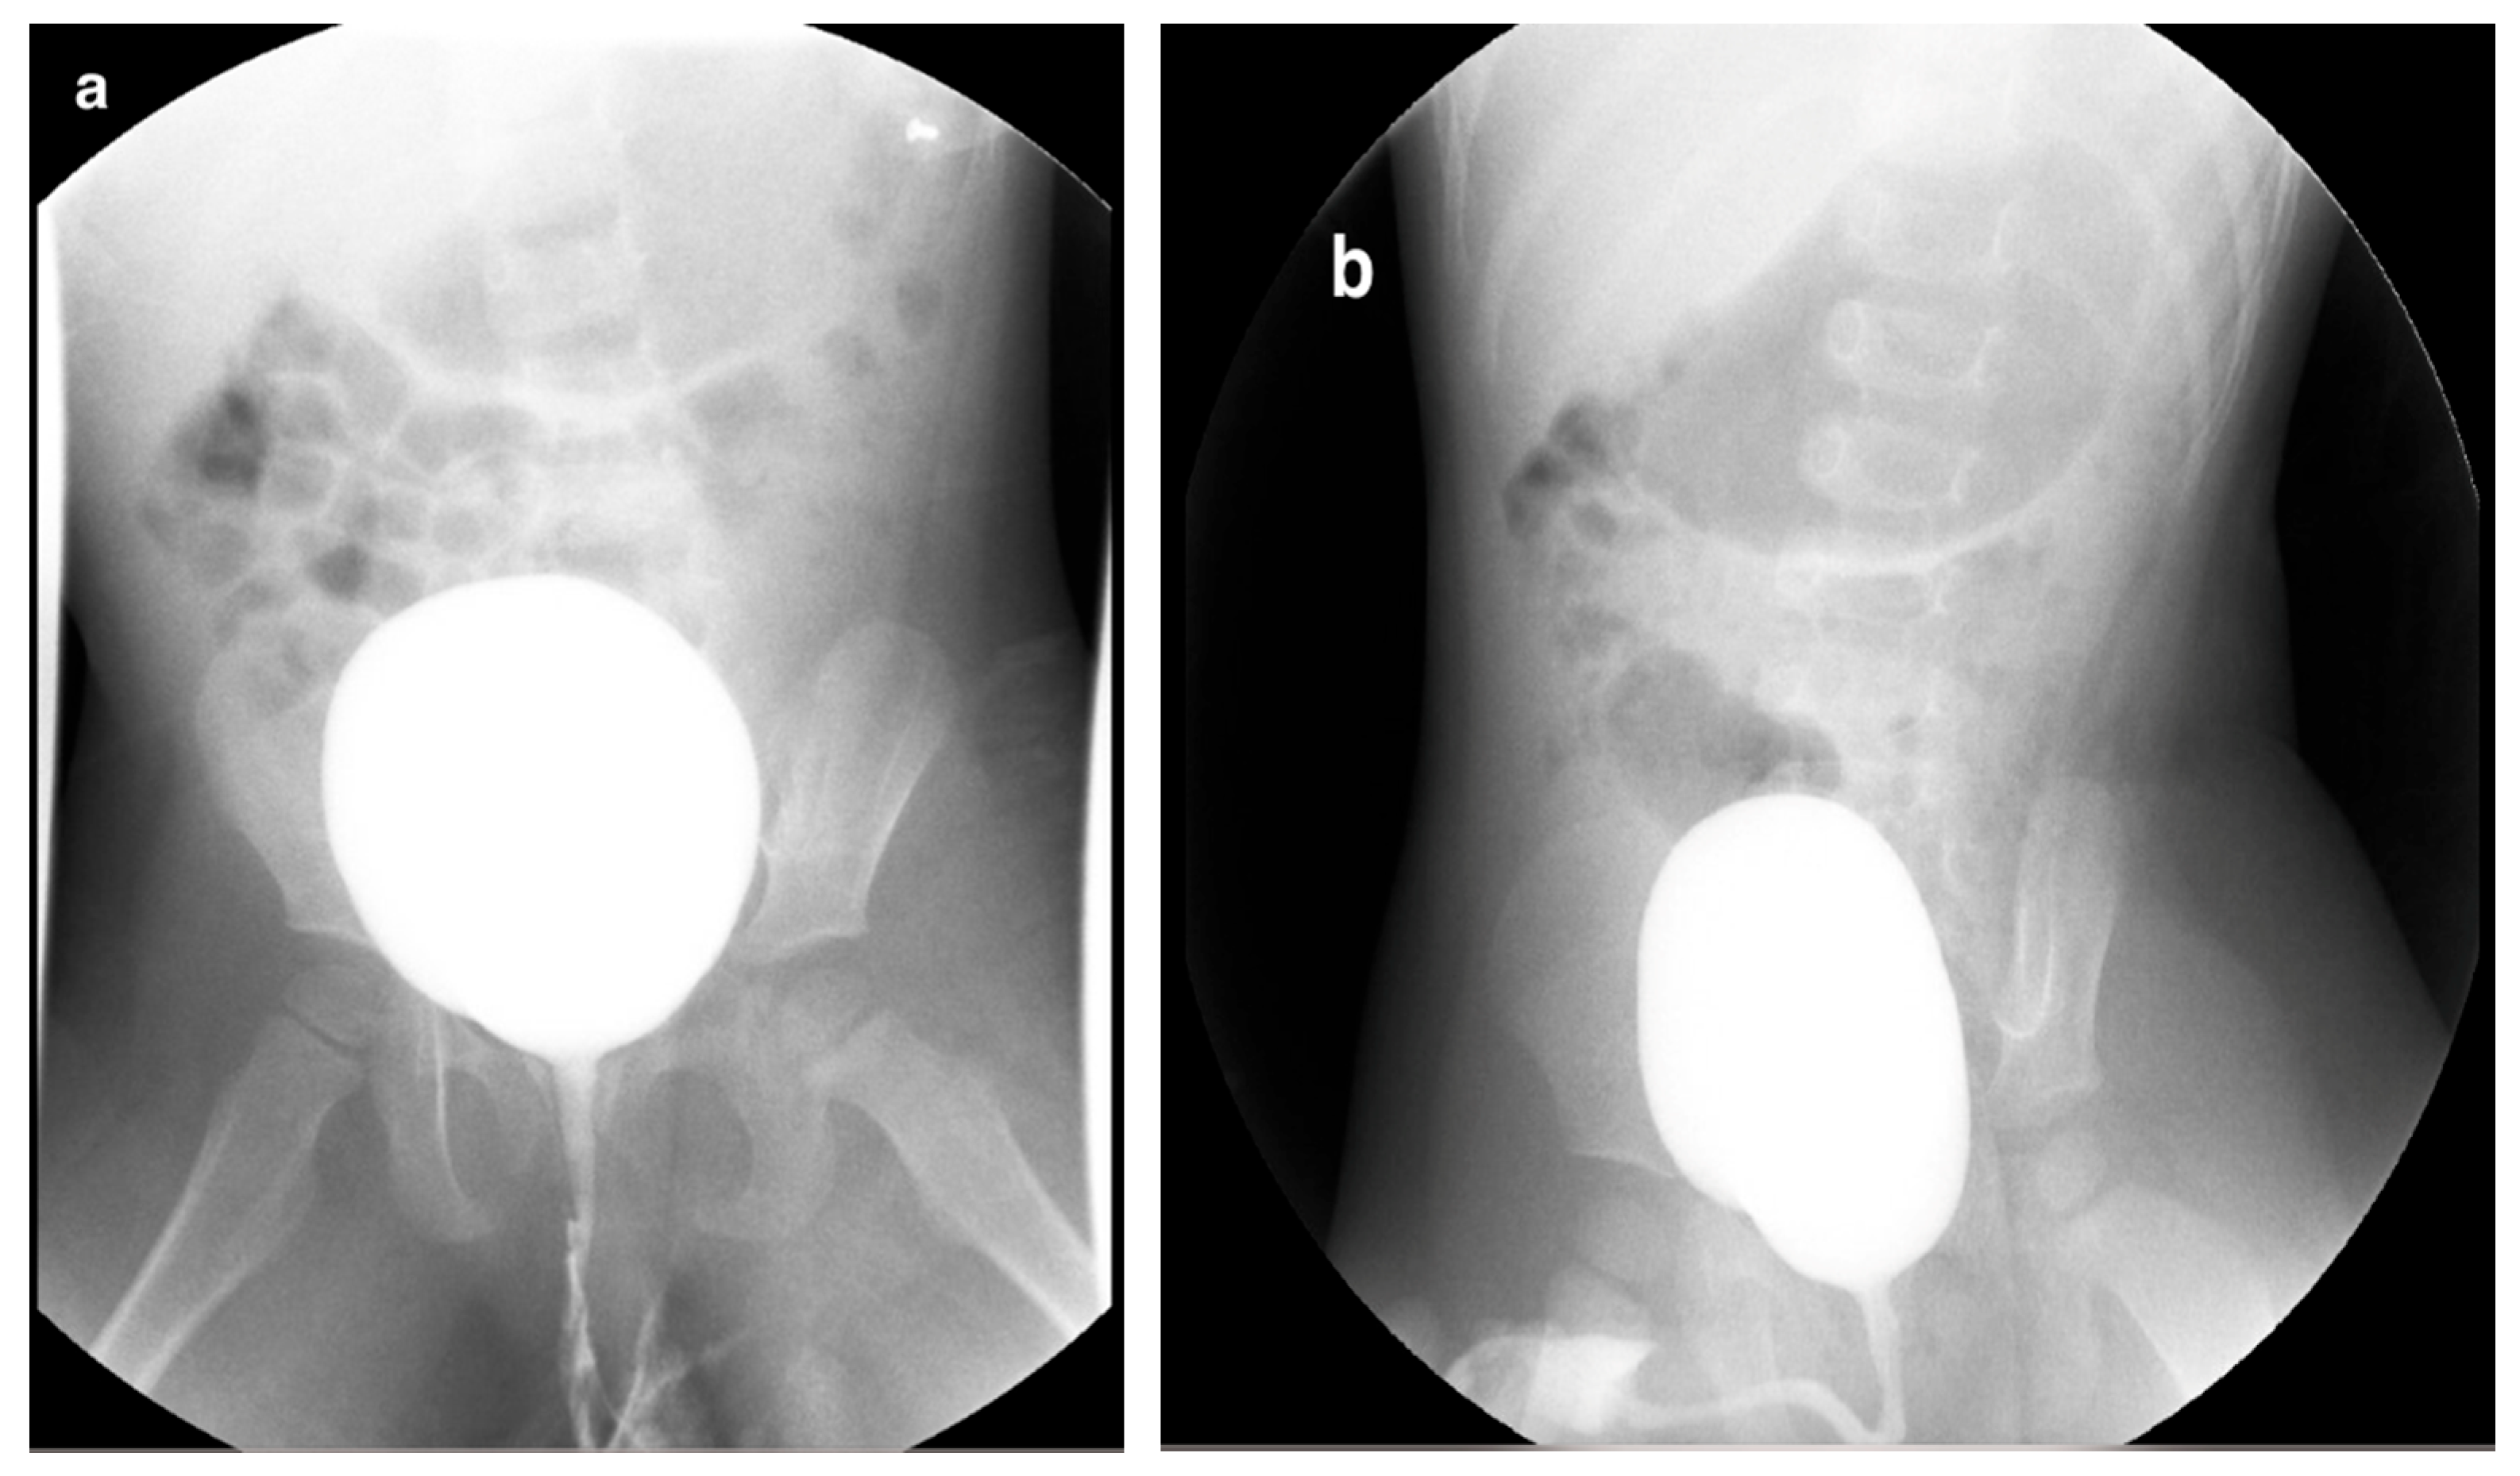

6. Voiding Cystourethrography (VCUG)

6.1. Procedure

6.2. Application

6.3. Complications

6.4. Limitations